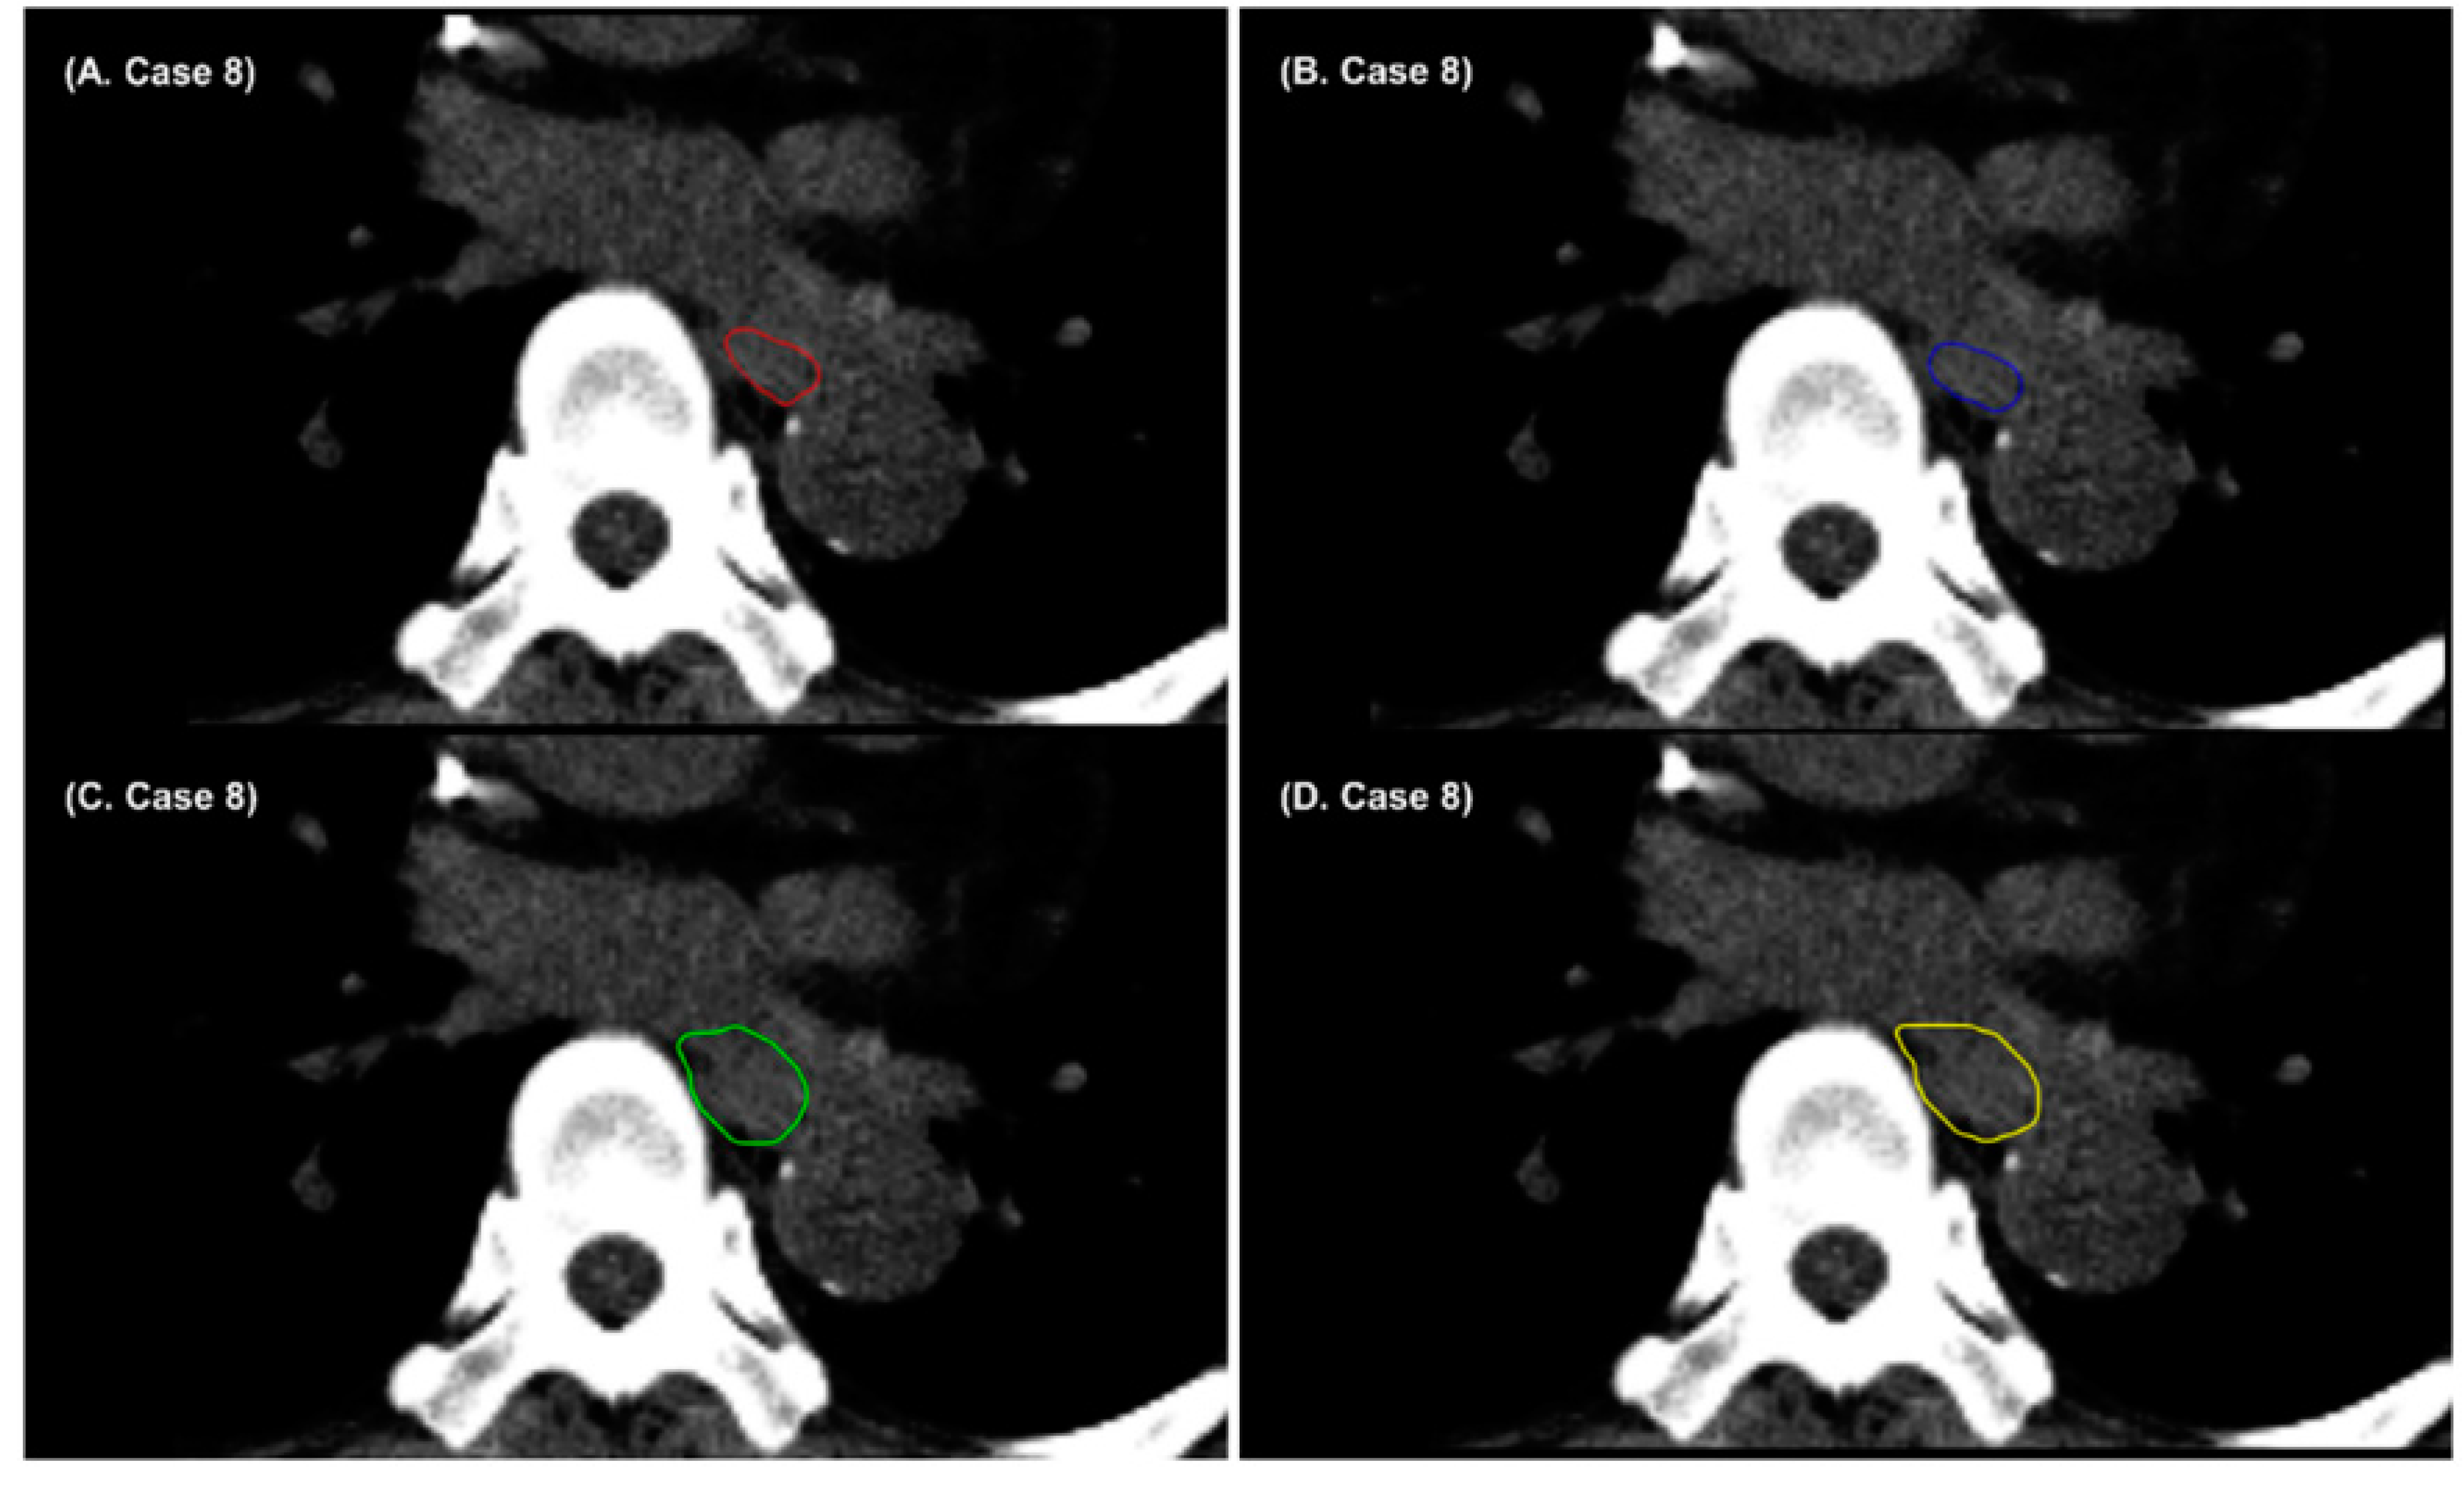

3. Results

4. Discussion